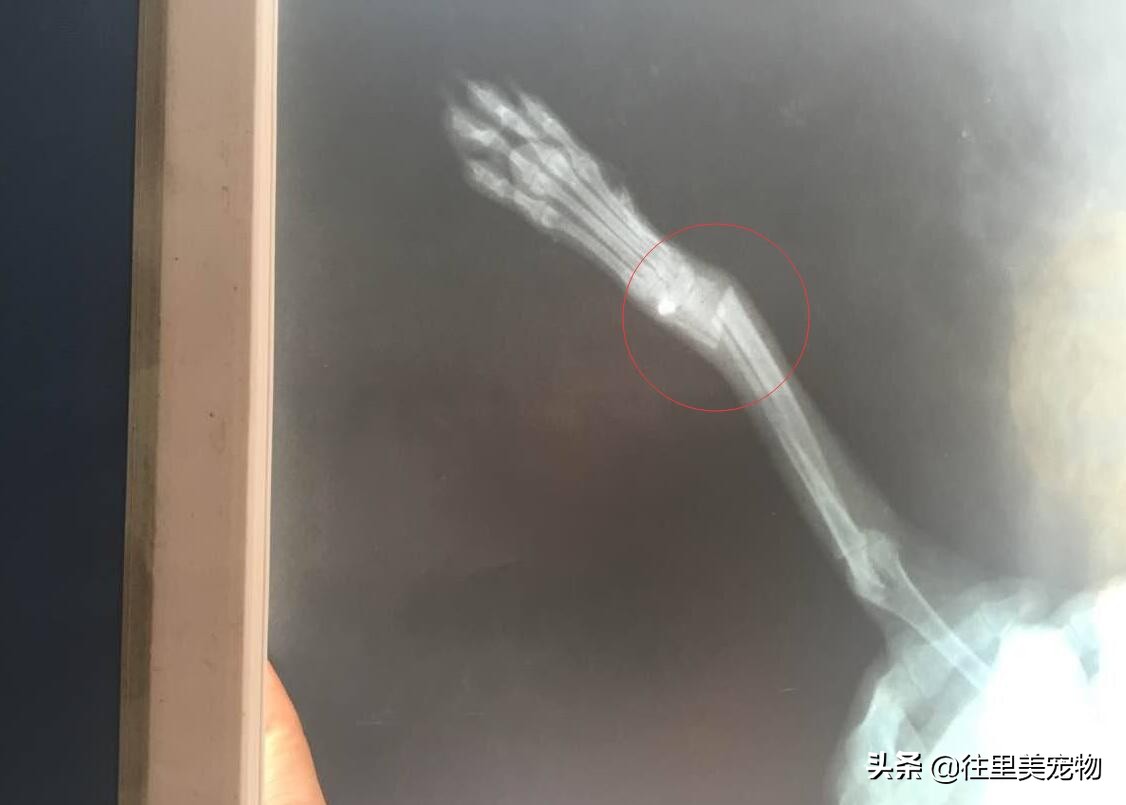

狗狗腿骨折的X光图片

骨折是狗狗最常见的外科疾病之一,大多是在外力的撞击或击打作用下,使骨的完整性和连续性受到破坏,同时伴有周围组织的损伤。临床上主要以四肢骨折为多见,尤其后肢。患犬局部肿胀、疼痛、变形或出现异常角度,触摸时骨折骨端有摩擦感。

狗狗骨折的治疗以紧急救护,复位,固定,促进愈合和恢复功能为主。

X光照射以后,准确找到骨折部位,因为狗狗受伤以后,患处会剧烈疼痛,同时自身也会十分的紧张,所以要想给予及时的治疗,首先要对它进行局部或全身麻醉,然后采取按、压、拉等方法,使移位的骨折部位重新复位,临床上越早复位越好。